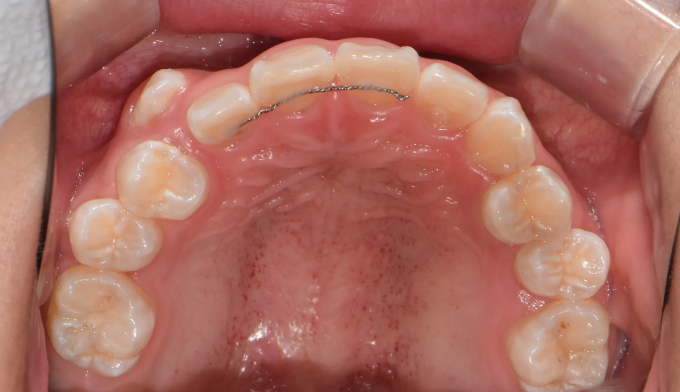

초등학생때 1차교정을 통해 앞니만 배열하였다고 했습니다.

진단해보니 송곳니가 나올 공간이 부족하여 2차교정을 진행하였습니다.

그래도 1차교정을 통해 공간을 어느정도 확보해 놓은것이 2차교정을 더 수월하게 해줍니다.

남아있는 공간을 최대한 활용하여 발치없이 치아를 배열해줍니다.